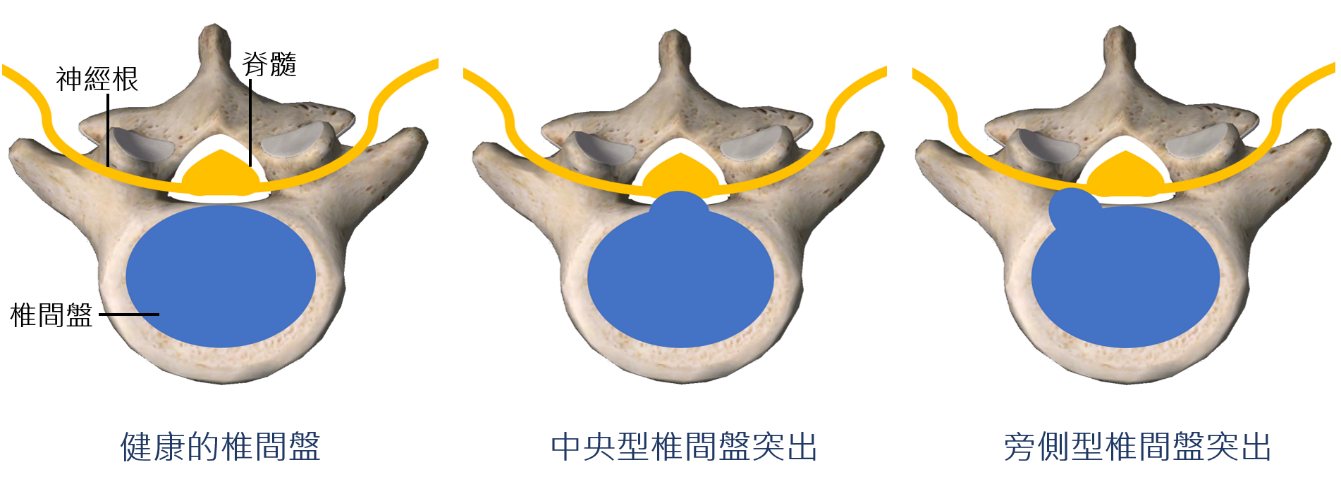

人體有五節的腰椎及一節的薦椎,椎體之間會有椎間盤,每個椎間盤都可能發生突出,不過最常見的突出發生在第四與第五節腰椎之間,或是第五腰椎與薦椎之間。椎間盤突出時,容易壓迫到周邊的脊隨與脊隨所分出的神經根,造成下肢的痠麻,這就是大家所俗稱的「坐骨神經痛」。神經壓迫嚴重時,也可能會造成下肢無力以及大小便失禁的情形;若是如此,應該要儘速就醫。

依照突出的位置決定治療方式

目前臨床上脊椎硬膜外注射與脊椎內視鏡手術都是很常見的治療方式也有各自的優勢。脊椎硬膜注射是局部麻醉的處置,在旁側型椎間盤突出可以迅速改善症狀,不會切除任何壓迫組織,所以風險相對於手術也較小。內視鏡手術適用在中央型及旁側型的椎間盤突出,雖然要全身麻醉,但是可以切除壓迫神經的組織。